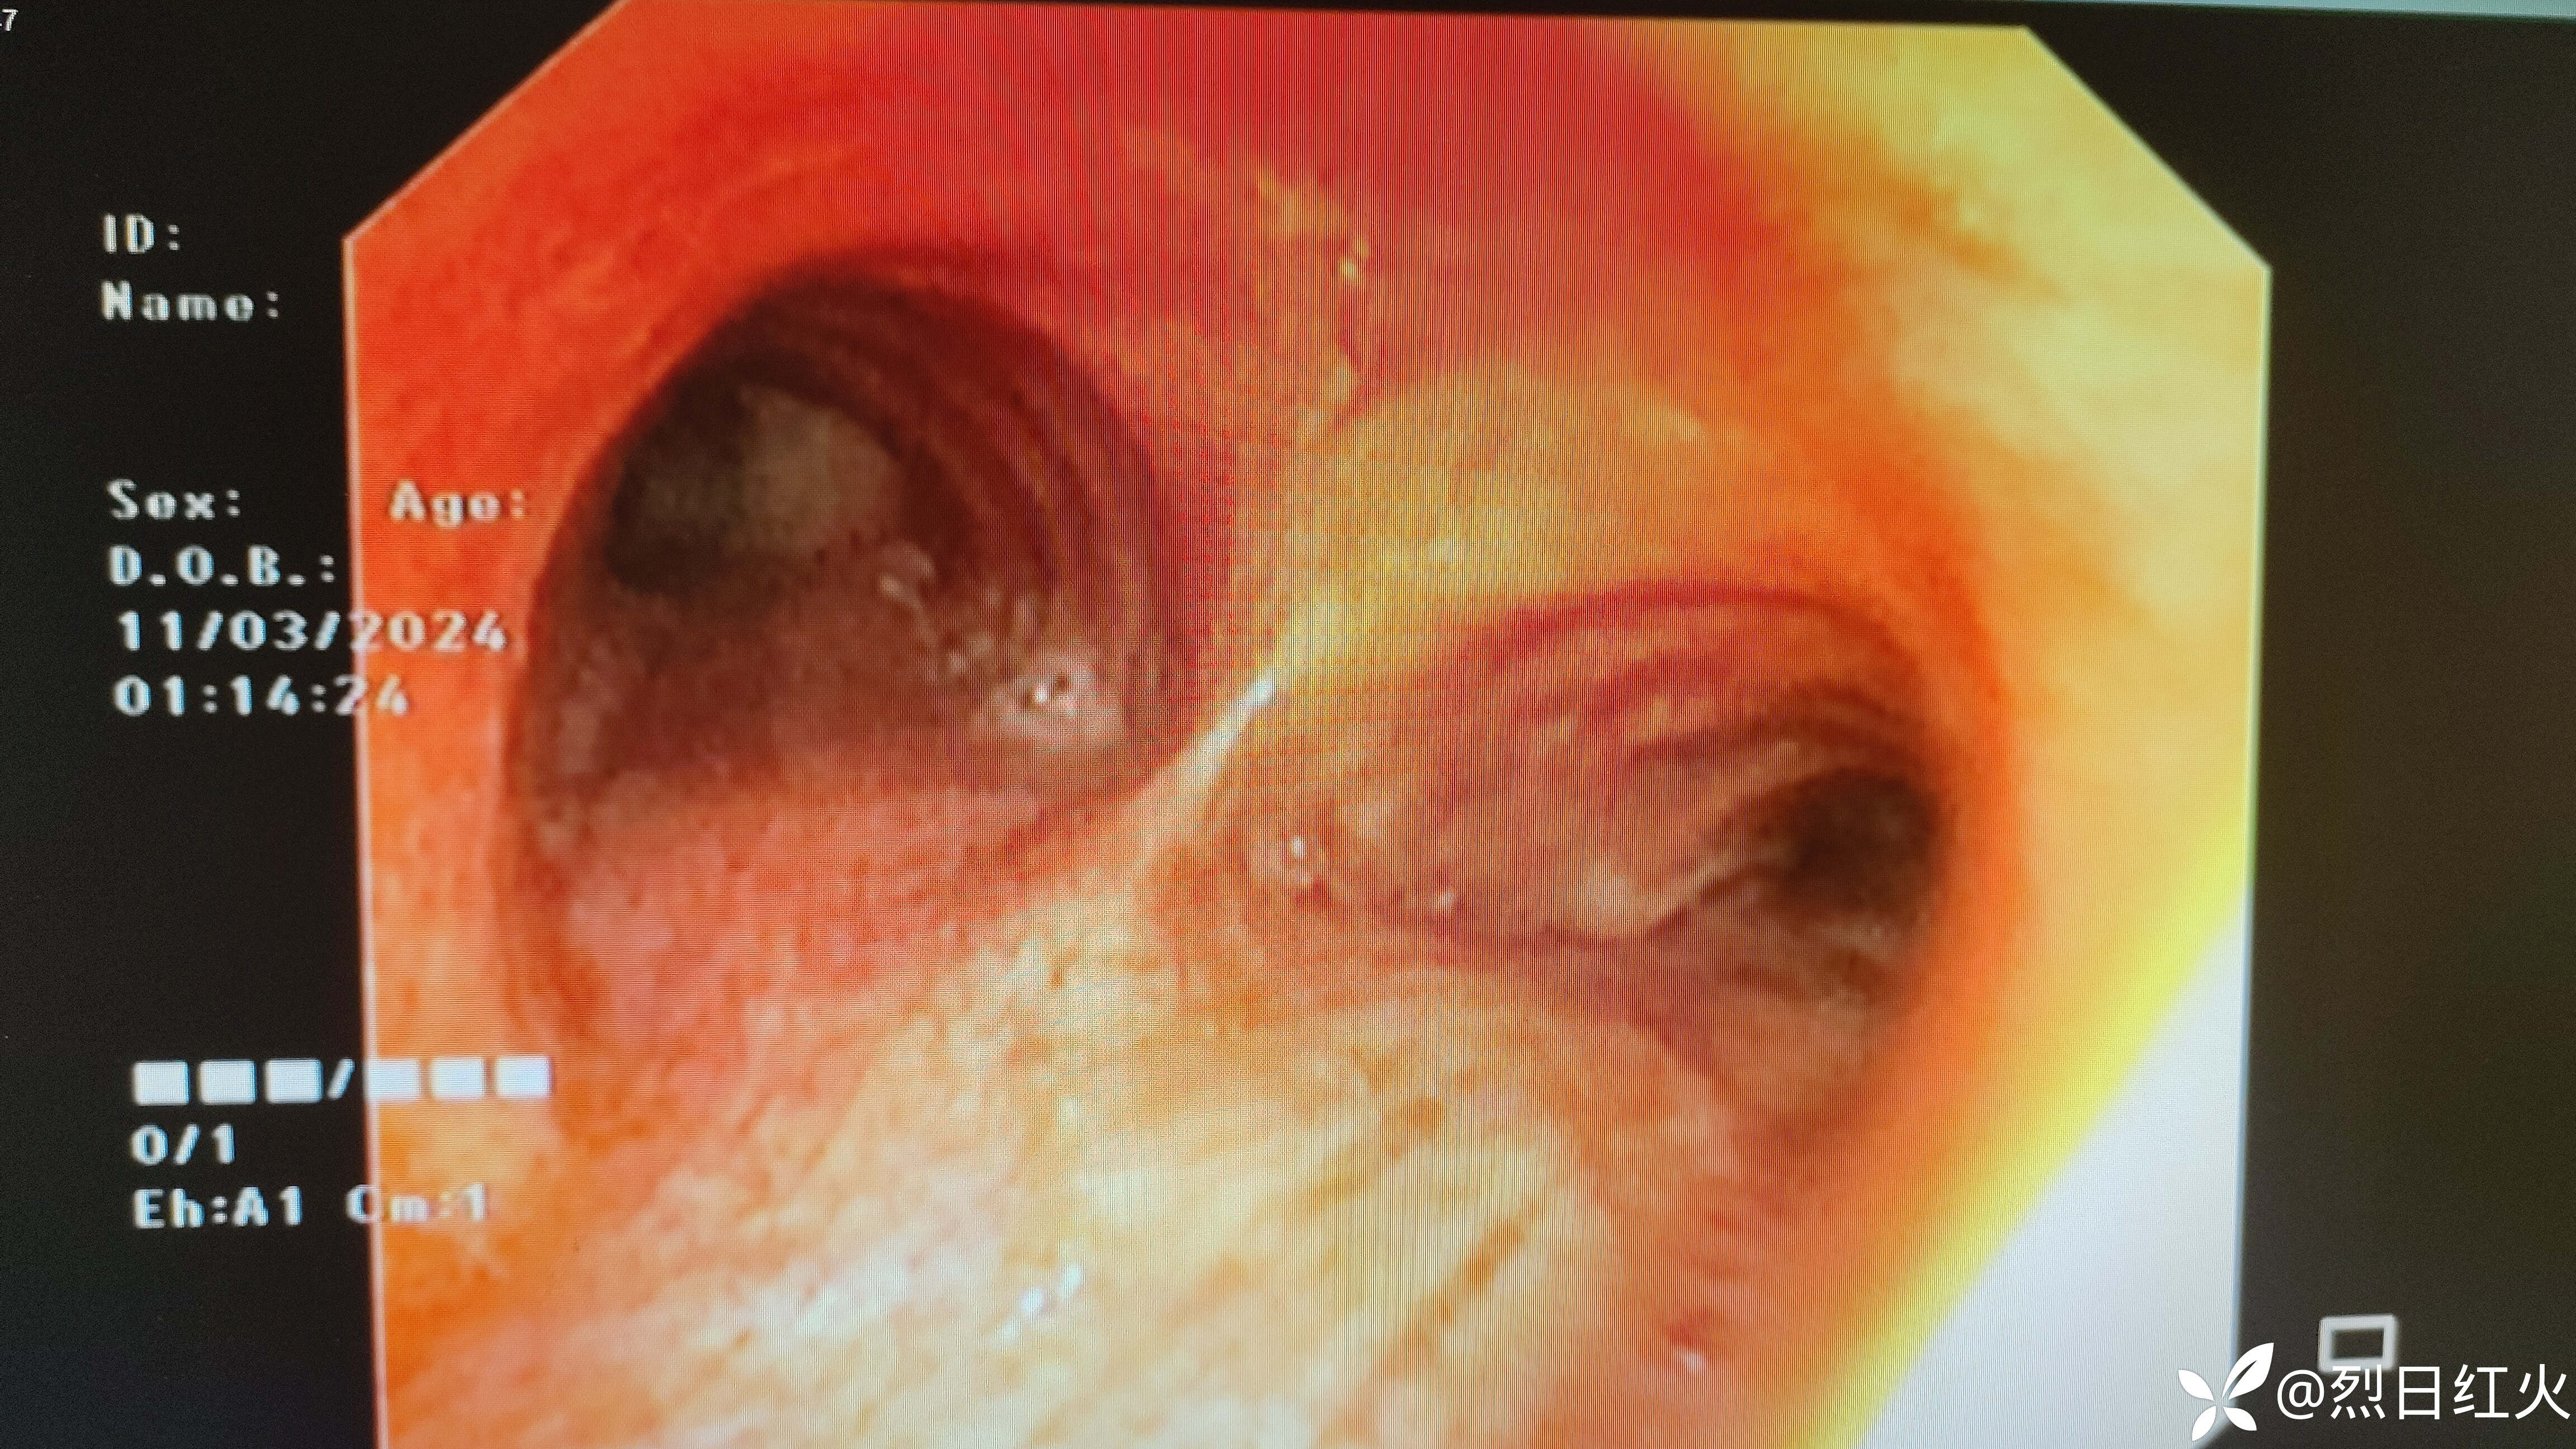

03-11纤维支气管镜检查

见支气管粘膜明显充血水肿。

03-14肺泡灌洗液示:少量曲霉菌生长

患者经抗感染症状有减轻,无发热,少量曲霉菌是否定植菌还是致病菌,结合入院时胸部CT定植菌可能性大!继续予以氨苄西林舒巴坦钠+左氧氟沙星抗感染